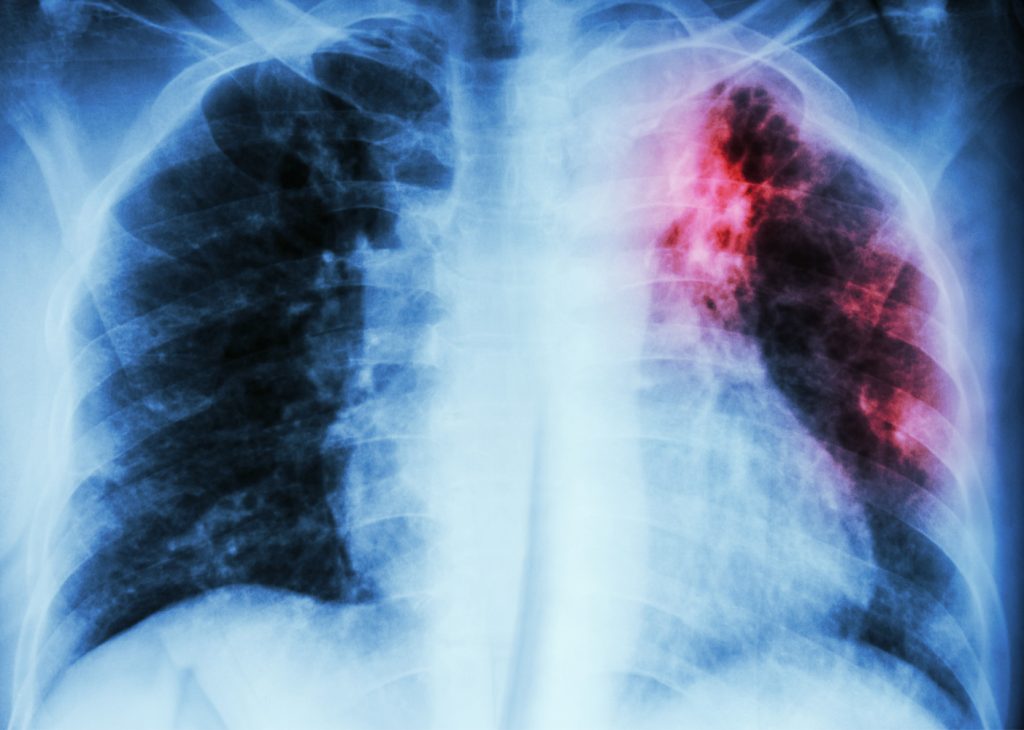

- Tuberculosis (TB) is a bacterial infectious disease caused by Mycobacterium tuberculosis, primarily affecting the lungs (pulmonary TB), but it can also involve other organs such as the brain, kidneys, and spine.

- Pulmonary TB: Affects the lungs; most common and contagious form

- Symptoms: Common symptoms of tuberculosis include persistent cough (sometimes with blood), fever with night sweats, weight loss and fatigue, and chest pain.